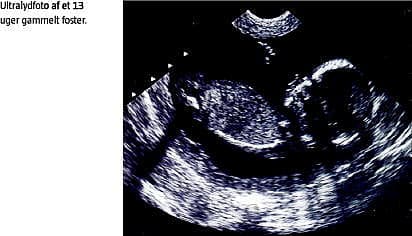

Hos patienter, der har få eller ingen risikofaktorer, et lavt antal aborter og ingen konceptionsproblemer, bør der ikke tilbydes aktiv terapi, men tæt monitorering omfattende gentagne målinger af serum-humant choriongonadotropin- og progesteronniveau samt ultralydskanninger i første trimester (tender loving care ). Alle patienter, der har haft AH, bør tilbydes ekstra monitorering i tredje trimester på grund af den øgede risiko for perinatale komplikationer.